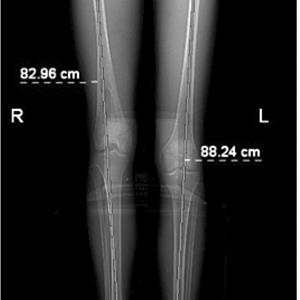

SCANOGRAM

FULL LENGTH X RAY OF BOTH LEG IN ONE FILM